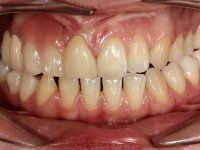

Female patient, 20 years old, non-smoker, had several surgical interventions to correct labial and palatal cleft. Patient presented a significant edentulous area between teeth 13 and 11, also due to the absence of teeth 12 and 15. Due to a traumatic impact, tooth 11 was non-vital, and extensively reconstructed with composite. Patient also had an orthodontic appliance with two prosthetic teeth and a buccal arch in this area to avoid teeth movement in this area. The area of the surgical correction of the labial and palatal cleft presented a significant deformity of hard and soft-tissues.

After the root canal treatment of tooth 11, dental impressions were taken to do a fixed provisional (reinforced) acrylic prosthesis. The provisional bridge included an acrylic component with a gum-shade color, to evaluate the integration of the treatment plan, in relation to function and esthetics. The preparation of teeth 14 and 13 were minimal invasive, with supra-gingival finishing lines, preserving enamel at its uttermost. Tooth 11 was prepared in a conventional way, with an intra-sulcular margin. The provisional bridge was rebased intra-oral with an autopolymerized acrylic. After 4 weeks, a dental impression with a double mixture technique was done. In the dental lab, CAD-CAM technology was used to produce a zirconia framework. In the provisional bridge, it was noted by the patient, and by ourselves, the need for symmetry in the dimensions and shape of the teeth, in relation to their homologues of the 2nd quadrant. Accordingly, a mirror effect was selected in the CAD design of the framework, to mimic in the prosthetic structure the dimensions and shape of the homologous natural teeth. Framework design included also a small zirconia wing covering the palatal surface of the non-prep tooth 21. This wing serves as an additional support and, simultaneously, avoids an eventual occurrence of a future diastema between central incisors. Color selection of teeth and soft-tissues was done by the ceramist in the dental office. After evaluation and approval of the prosthetic work placed in mouth, the dental bridge was bonded. This bonding procedure was optimized by the addition of a zirconia liner in the inner surface of the framework and in the internal surface of the wing. This treatment proved to be esthetically acceptable and functionally able, with a strong contribution to the patient’s self-esteem.